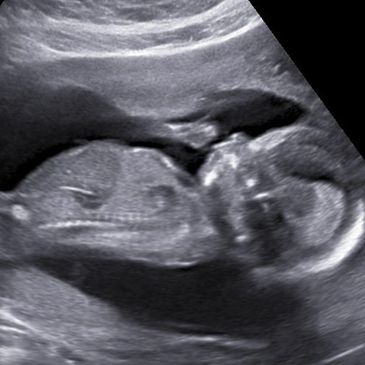

3d Ultrasound 4d Ultrasound Hd Ultrasound In Texarkana Ar